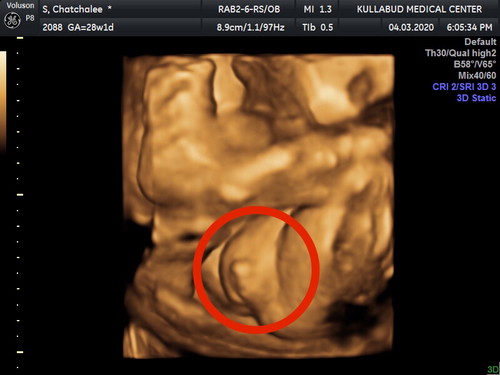

ไม่ต้องบอกเลยว่าลูกชายหรือลูกสาว..จิ๊มิชัดขนาดนี้555...ว่าแต่ดั้งหายไปไหนหมดลูก..โตมาค่อยไปทำละกันน้า❤️??